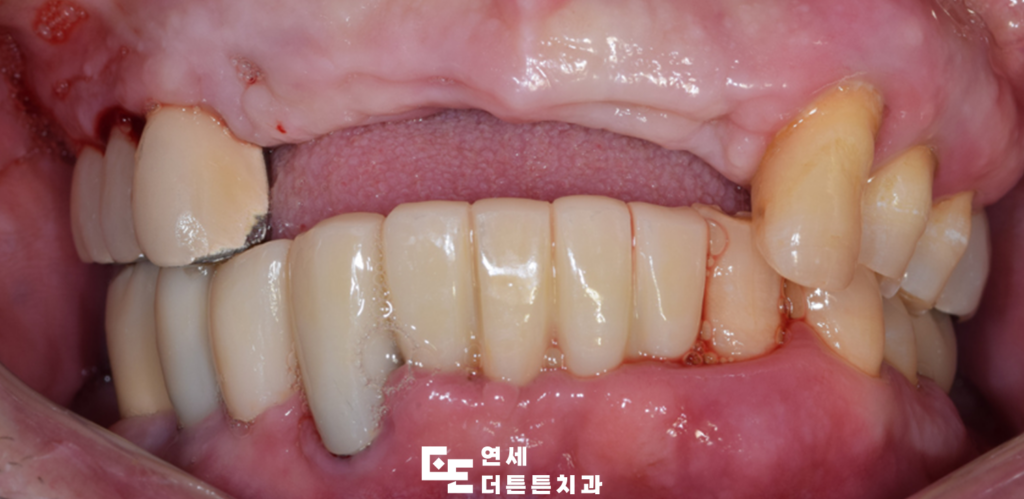

오늘은 염증이 심한 앞니 브릿지를 제거하고

앞니 임플란트를 진행하신

수락산역치과 환자분을

소개해 드리도록 하겠습니다.

수락산역치과 환자분께서는

오래전 씌웠던 앞니 브릿지가

흔들리는 느낌이 드신다며 내원해 주셨습니다.

겉으로 보기에는 문제가 없는 듯 보였으나

수락산역치과 연세더튼튼치과에서

최종 보철물까지 완성한 모습입니다.